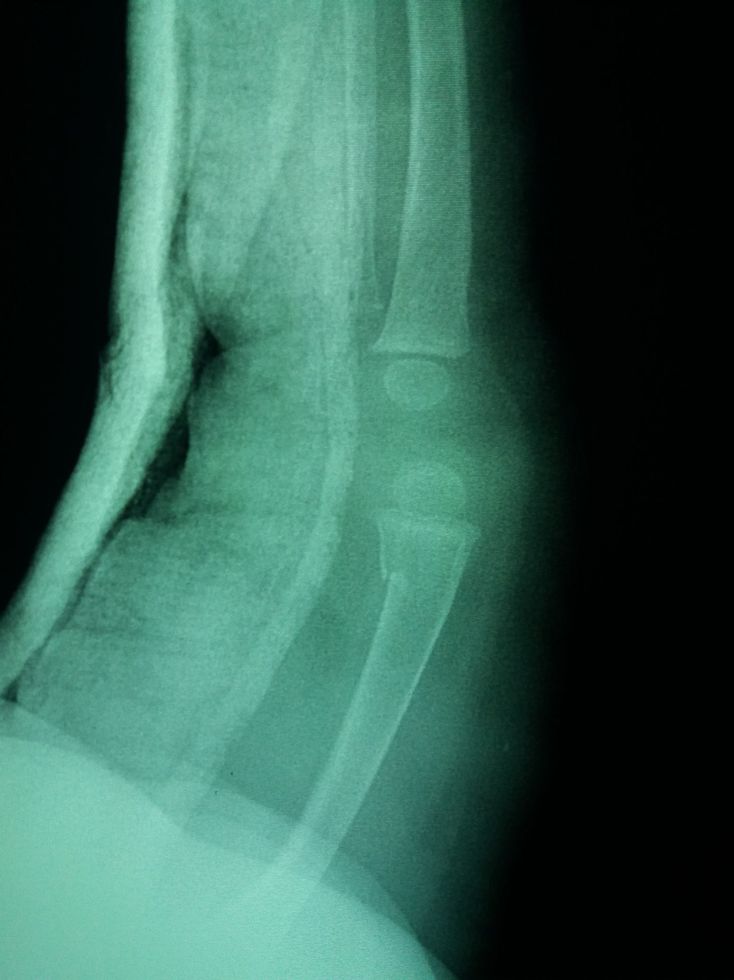

What do you see?

Trauma

Xray

Fracture

Child

Femoral

Greenstick fracture?